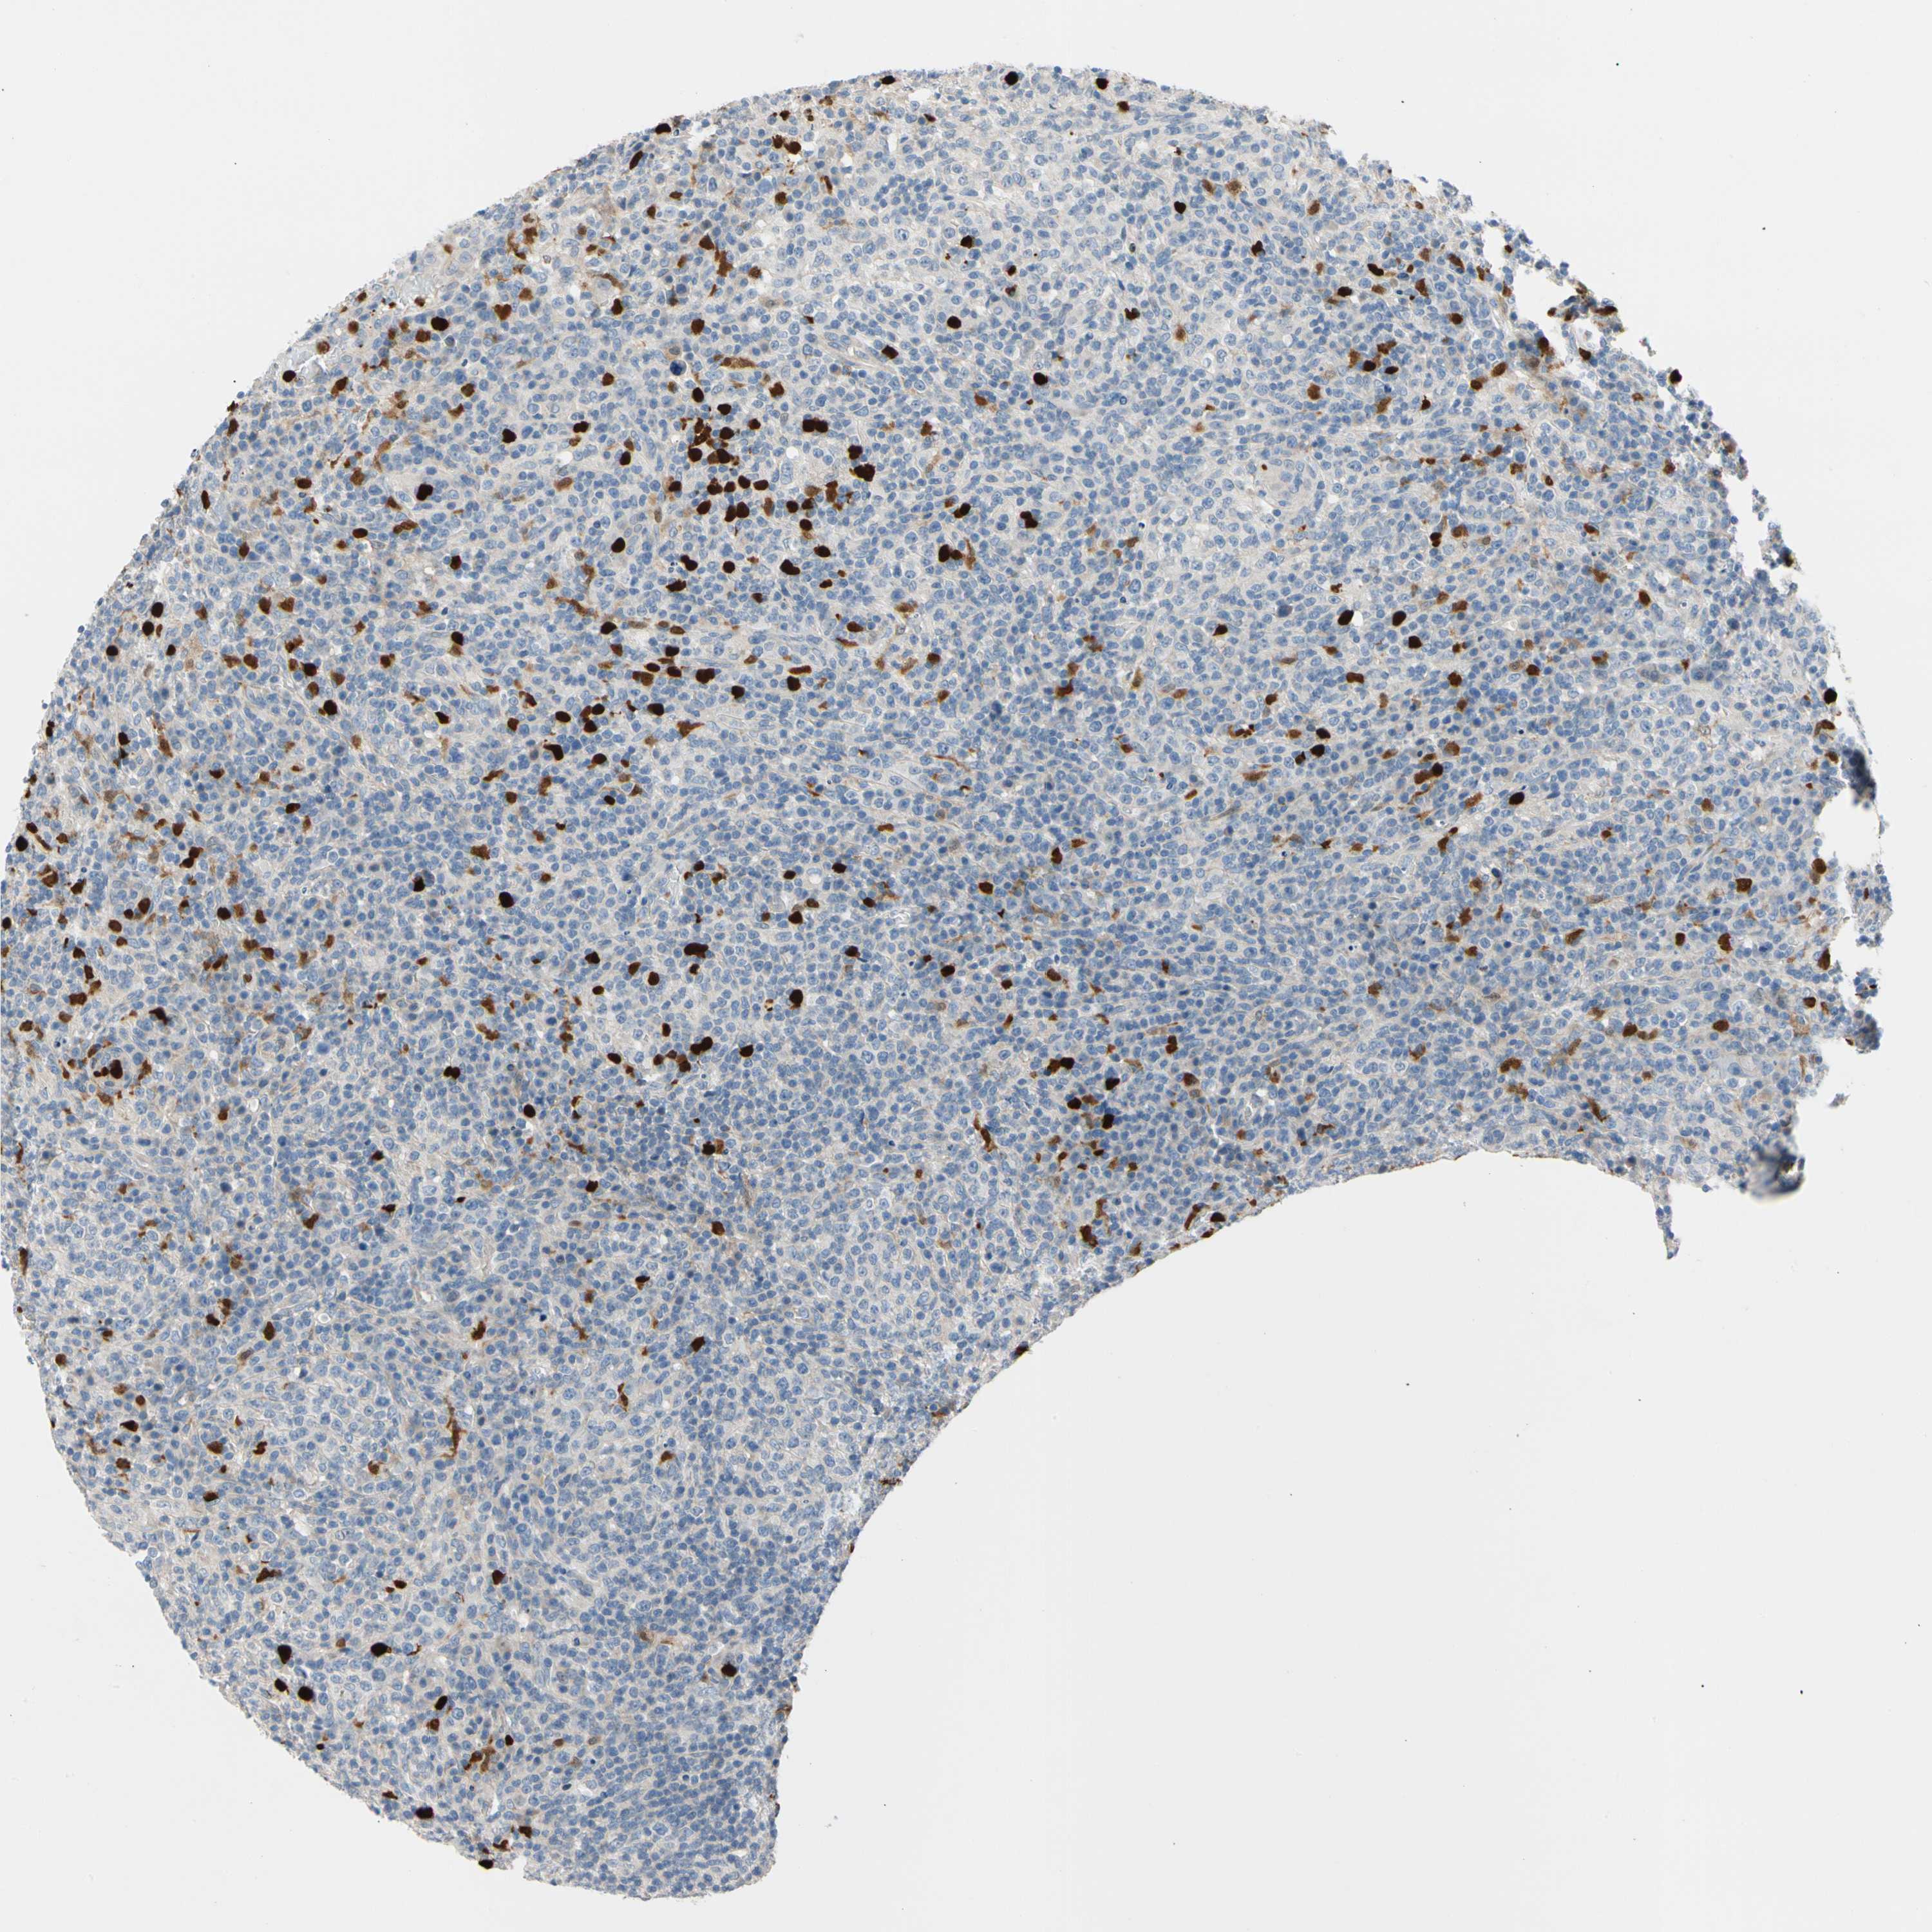

CANCER LYMPHOMA Show tissue menu

LYMPHOMA - Protein expressioni

A mouse-over function shows sample information and annotation data. Click on an image to view it in a full screen mode. Samples can be filtered based on level of antibody staining by selecting one or several of the following categories: high, medium, low and not detected. The assay and annotation is described here.

Antibody stainingi

Antibody staining in the annotated cell types in the current human tissue is reported as not detected, low, medium, or high, based on conventional immunohistochemistry profiling in selected tissues. This score is based on the combination of the staining intensity and fraction of stained cells.

Each image is clickable and will lead to virtual microscopy that enables deeper exploration of all samples and also displays staining intensity scores, fraction scores and subcellular localization as well as patient and tissue information for each sample.

Antibody HPA008052

Antibody CAB010277

Staining

High

Medium

Low

Not detected

Intensity

Strong

Moderate

Weak

Negative

Quantity

>75%

75%-25%

<25%

None

Location

Nuclear

Cytoplasmic/membranous

Cytoplasmic/membranous,nuclear

Hodgkin's disease, NOS

Malignant lymphoma, non-Hodgkin's type, Low grade

Malignant lymphoma, non-Hodgkin's type, High grade